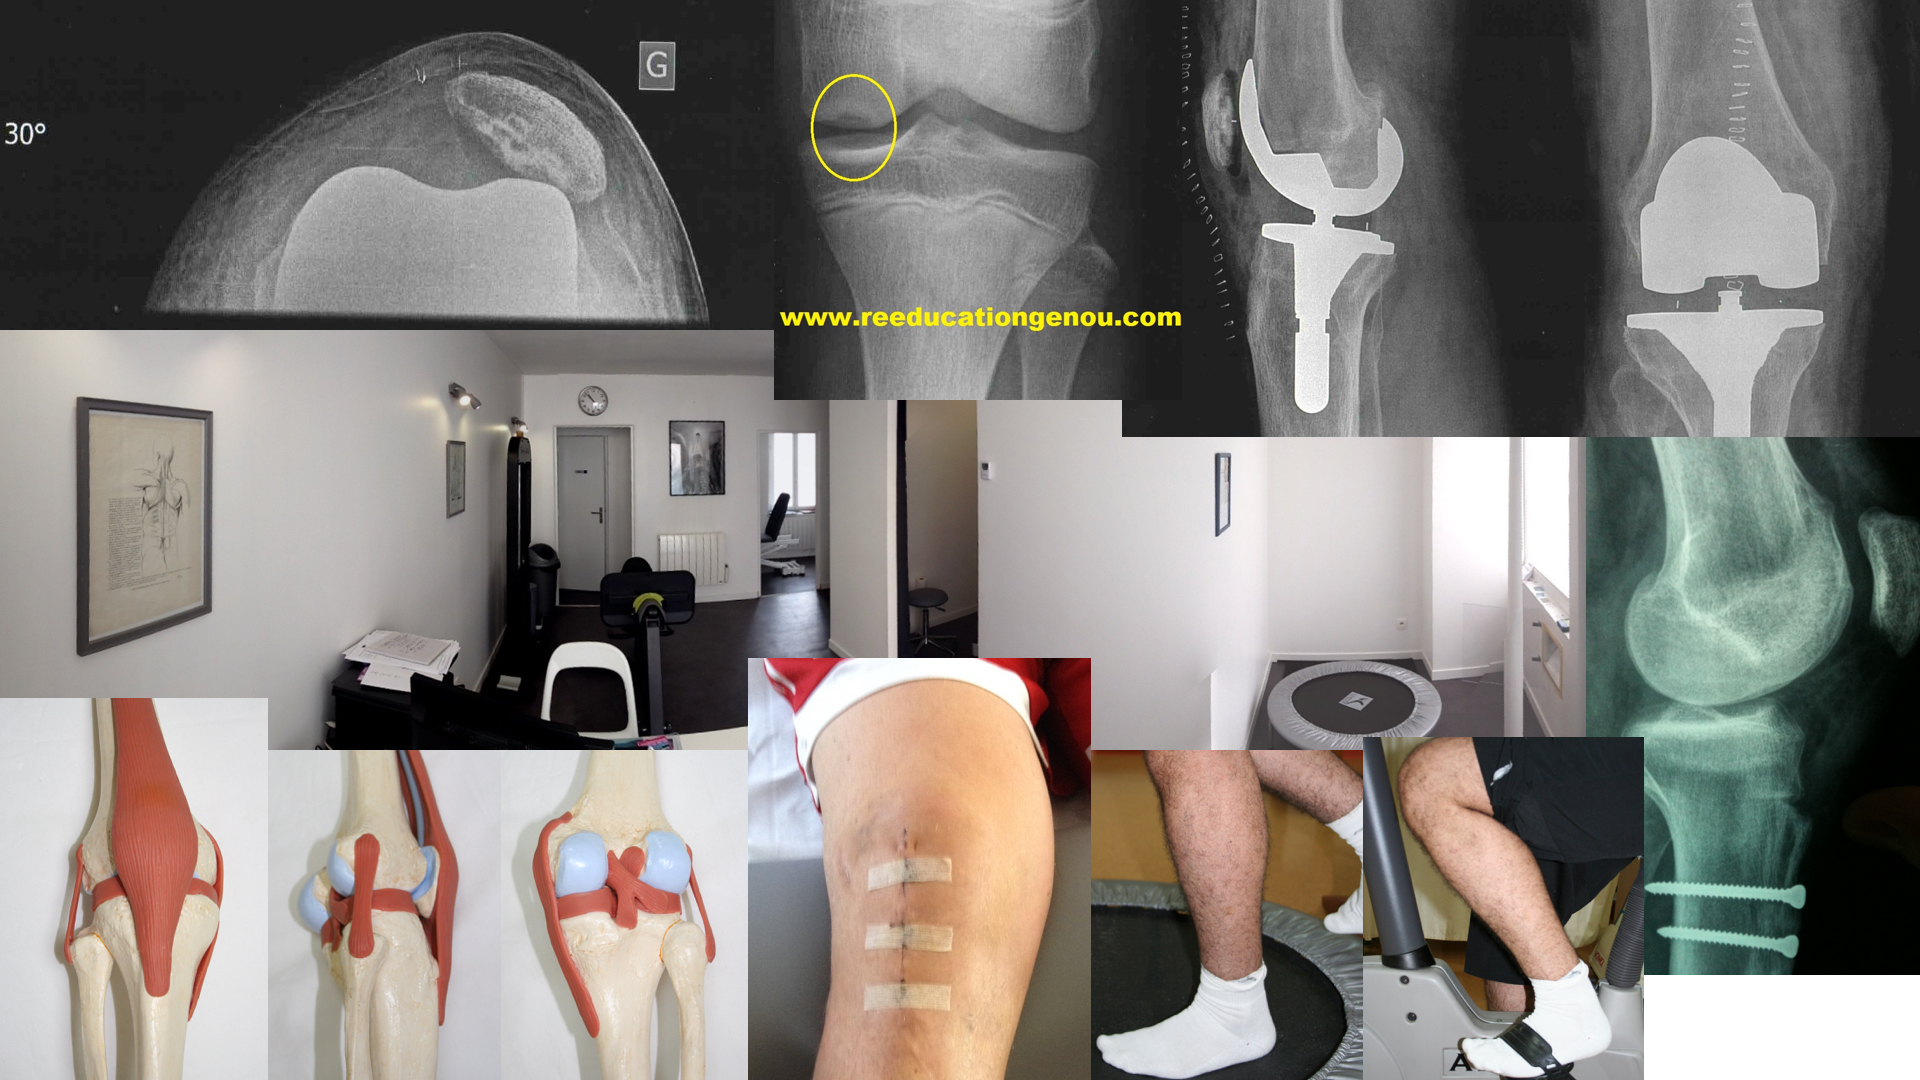

4ème au 6è mois : tests fonctionnels, retour sur terrain

La période de reprise sportive "cadrée" : du 4-5ème au 12ème mois voire 2 ans

C'est la période où le patient est confronté aux résultats de sa rééducation initiale. Chacun doit prendre son temps.

c'est aussi la phase où l'on intensifie la préparation physique et la réathlétisation